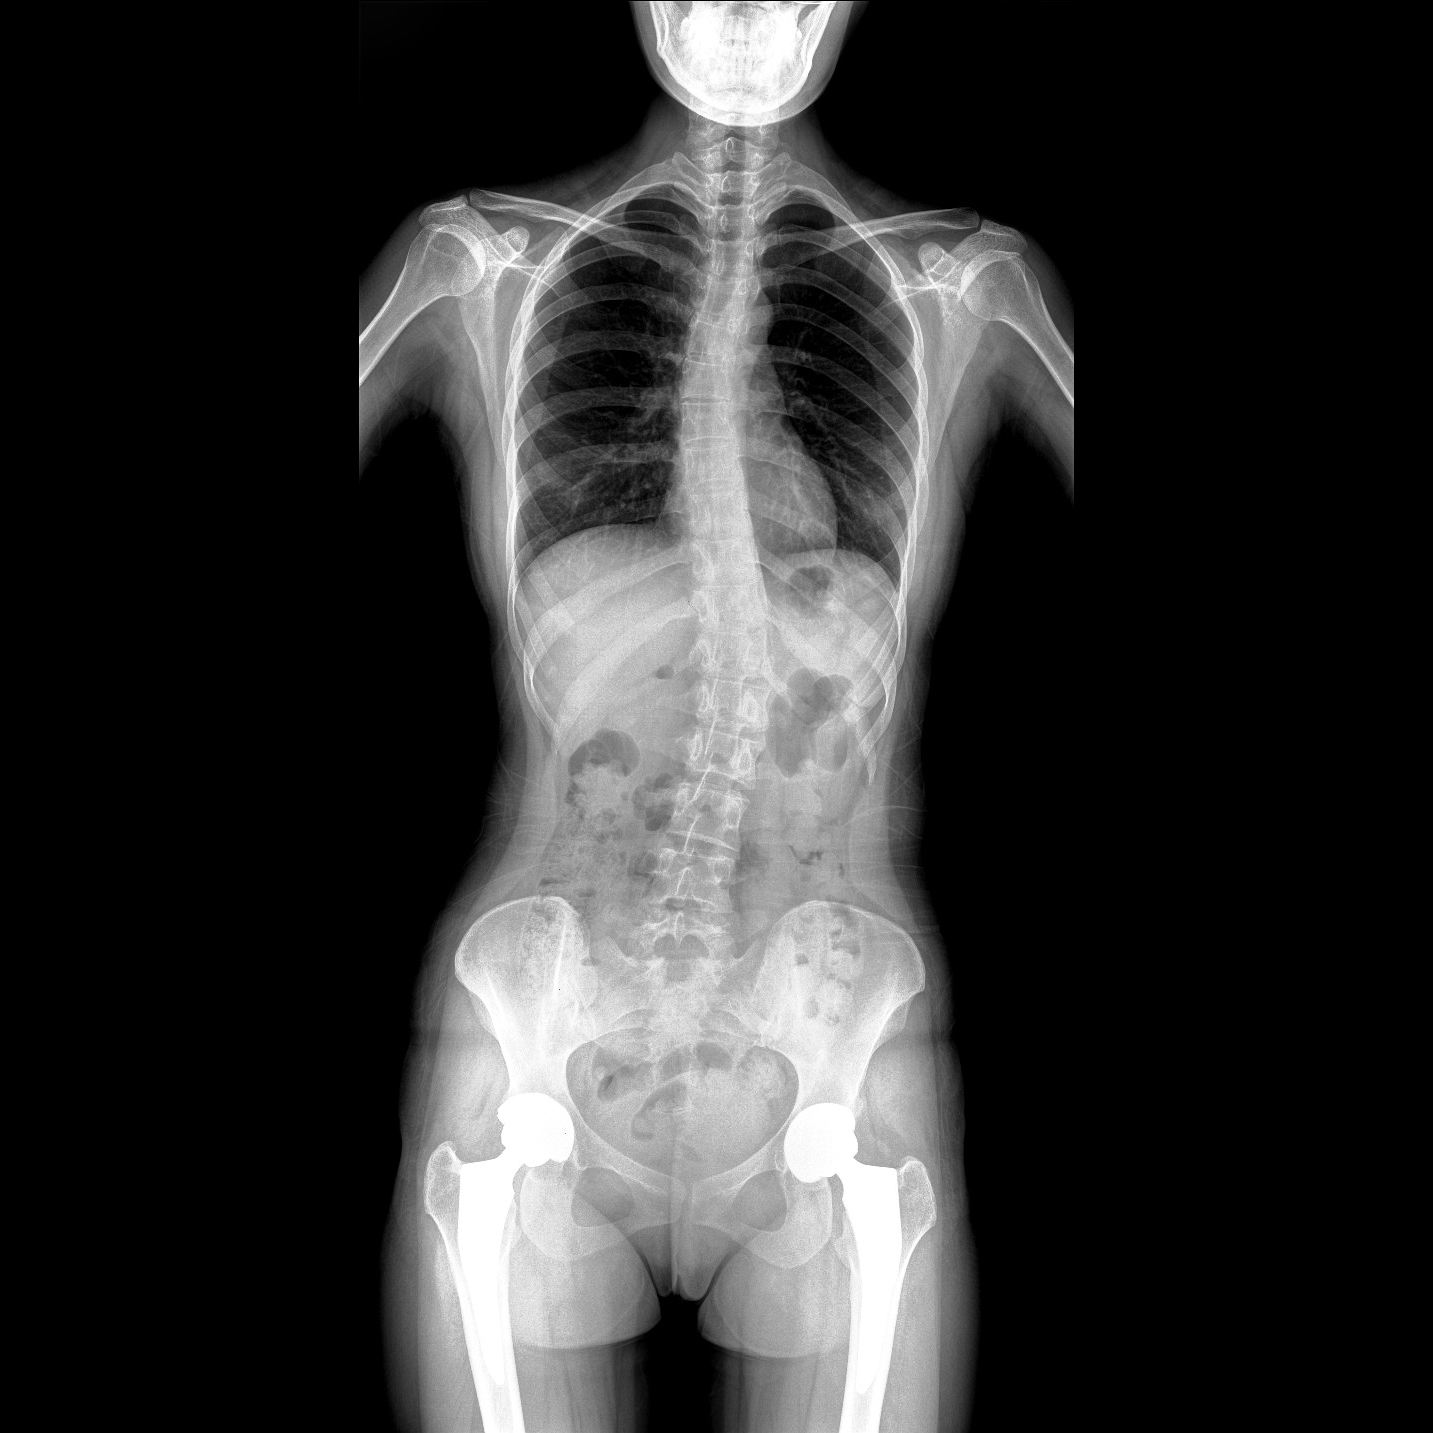

支持全脊柱攝影、雙下肢攝影、脊髓造影、復(fù)雜創(chuàng)傷、人工關(guān)節(jié)置換、關(guān)節(jié)損傷的修復(fù)重建等大視野臨床應(yīng)用

除常規(guī)靜態(tài)攝影外,PLX8600大平板具備動態(tài)透視和點片功能,透視采集功能可支持大視野、多角度的可視化觀察。通過可視化的動態(tài)影像,配合點片功能,能夠很好的觀察復(fù)雜部位病灶,有效的抓取關(guān)鍵幀,降低患者多次攝片的概率。如:全脊柱狀態(tài)評估、長骨關(guān)節(jié)活動度、下肢靜脈造影瓣膜功能評估、消化道功能評估、脊髓造影等更多大視野臨床應(yīng)用。